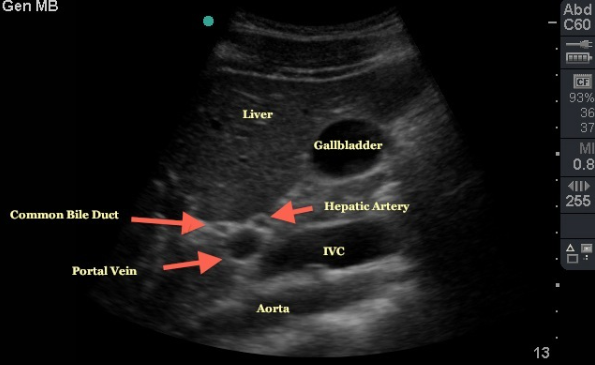

Portal Triad

Portal vein

bile duct

hepatic artery

the COMMON hepatic duct is located anterior to the portal vein and lateral to the hepatic artery in its caudal descent from the porta hepatis

the COMMON hepatic duct runs PARALLEL with the PORTAL VEIN, travels medially in the body and is joined by the CYSTIC DUCT to form the COMMON BILE DUCT

continues caudal descent along hepatic artery and portal vein